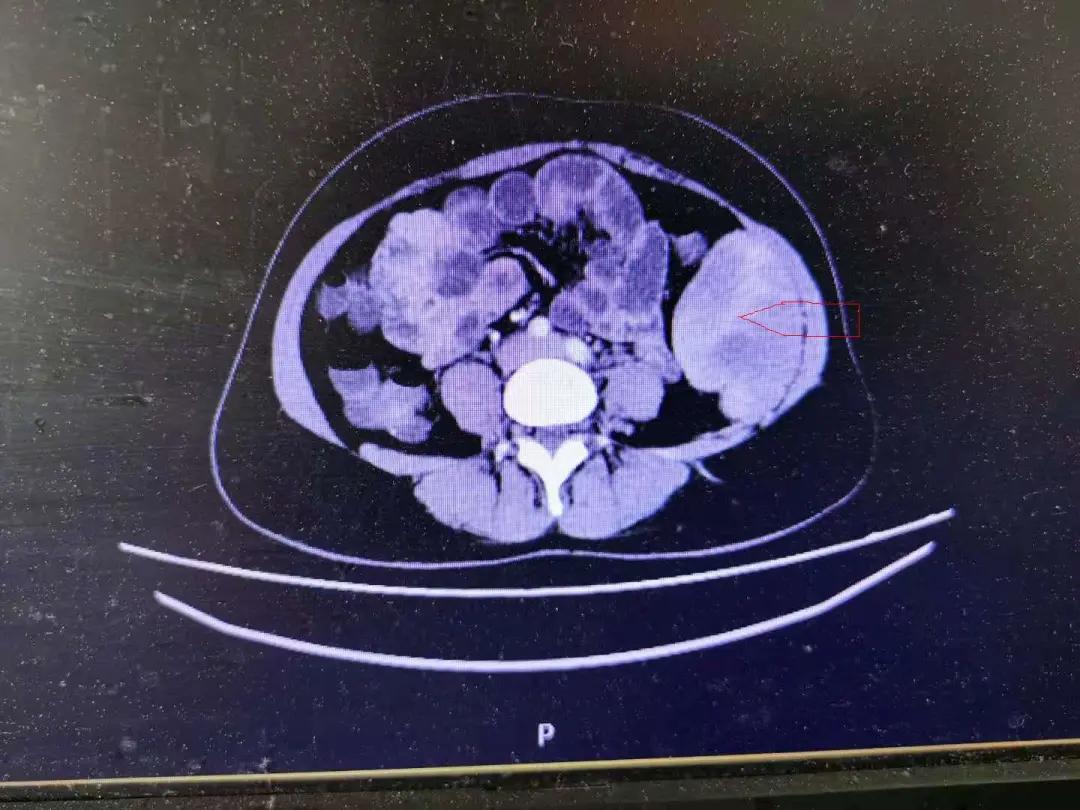

强化CT,可见肿瘤呈中度强化

成功切除巨大梭形细胞瘤

患者女性,37岁,因“发现左侧腹部包块2月”入院,既往有“剖宫产史”。入院查体可见腹部平坦,下腹部陈旧性手术疤痕,腹软,左侧腹部可触及质硬包块,有压痛、无反跳痛,直径约10*6cm,边界欠清,活动度差。腹部超声示左侧腹腔低回声包块,114*90*54mm,边界尚清,形态欠规则,回声不均匀;腹部CT示左侧中腹部腹腔巨块状软组织密度影,分叶改变,6.4*8.6*9.5cm,腹膜后结构清晰,无肿大淋巴结。入院后行肿瘤标记物及结肠镜等检查结果无明显异常,术前分别请泌尿外科及妇科会诊,基本排除泌尿肿瘤及妇科肿瘤的可能性。

经过充分的术前评估及积极的术前准备,手术团队在全麻下对该患者实施了腹腔镜腹腔肿瘤切除术。术中探查见肿瘤位于腹膜后,延至左侧腹壁,12*6*5cm大小,质硬,包膜完整,肿瘤压迫左侧输尿管及局部肠管,腹壁无转移灶,肝胆胰脾及左侧附件等脏器表面无明显异常。因瘤体体积较大且富含滋养血管,并且与左侧腹壁下血管、左侧腹壁肌肉、左侧输尿管及部分肠管等重要组织解剖关系紧密,所以手术难度及手术风险大大增加。团队在手术过程中配合熟练、胆大仔细,最终成功将巨大瘤体完整切除,术后病理结果示:梭形细胞瘤(肿瘤12×9×6cm),细胞轻度异型,未见核分裂相,结合免疫组化考虑非典型血管纤维瘤,切缘未见癌细胞,CD117阴性。术后1周患者痊愈出院。